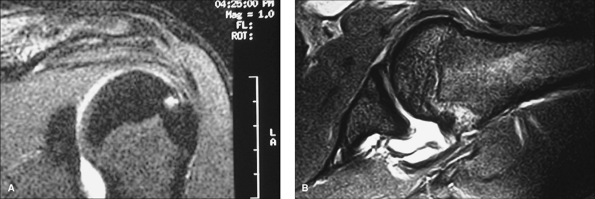

with a gadolinium arthrogram. These lesions are typically not seen on

to consider the inclusion of a series that positions the arm in an

abducted and externally rotated position. It is not rare to see what

appears to be a small and insignificant tear become a rather large tear

with this maneuver (Fig. 38-2).

|  |

| Figure 38-2 A: Coronal MRI (T2) view of a patient with clinical signs consistent with a partial rotator cuff tear. B: MRI (T2) view in abduction and external rotation depicting a near full-thickness tear of the supraspinatus. |